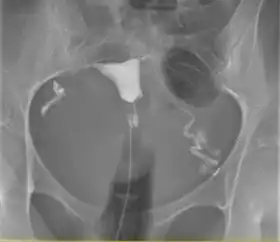

A normal hysterosalpingogram. Note the catheter entering at the bottom of the screen, and the contrast medium filling the uterine cavity (small triangle in the center).

Hysterosalpingography (HSG), also known as uterosalpingography,[1] is a radiologic procedure to investigate the shape of the uterine cavity and the shape and patency of the fallopian tubes. It is a special x-ray procedure using dye to look at the womb (uterus) and fallopian tubes.[2] In this procedure, a radio-opaque material is injected into the cervical canal, and radiographs are taken. A normal result shows the filling of the uterine cavity and the bilateral filling of the fallopian tube with the injection material. To demonstrate tubal patency, spillage of the material into the peritoneal cavity needs to be observed. Hysterosalpingography has vital role in treatment of infertility, especially in the case of fallopian tube blockage.

The procedure involves x-rays (fluoroscopy).[7] Images are taken to demonstrate the filling of endometrial cavity, which shows full view of the fallopian tubes demonstrating the spillage of contrast material into peritoneum, the extent of the block if no spillage is present, or a delayed view in the case of abnormal cavities (locule) within. Subject may have vaginal spotting for one to two days, accompanied with pain that may persist for up to two weeks. Some medical centres routinely give prophylactic antibiotics before subject is allowed home.[3]